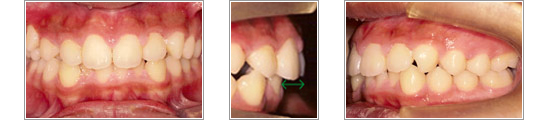

写真左:上の前歯のでこぼこがなくなりました。

写真中、右:上の前歯と下の前歯の距離が治療前の約1/3になりました。

第2期治療で、でこぼこが残っているところをまっすぐな歯並びにし、また咬み合わせを整えていきます。